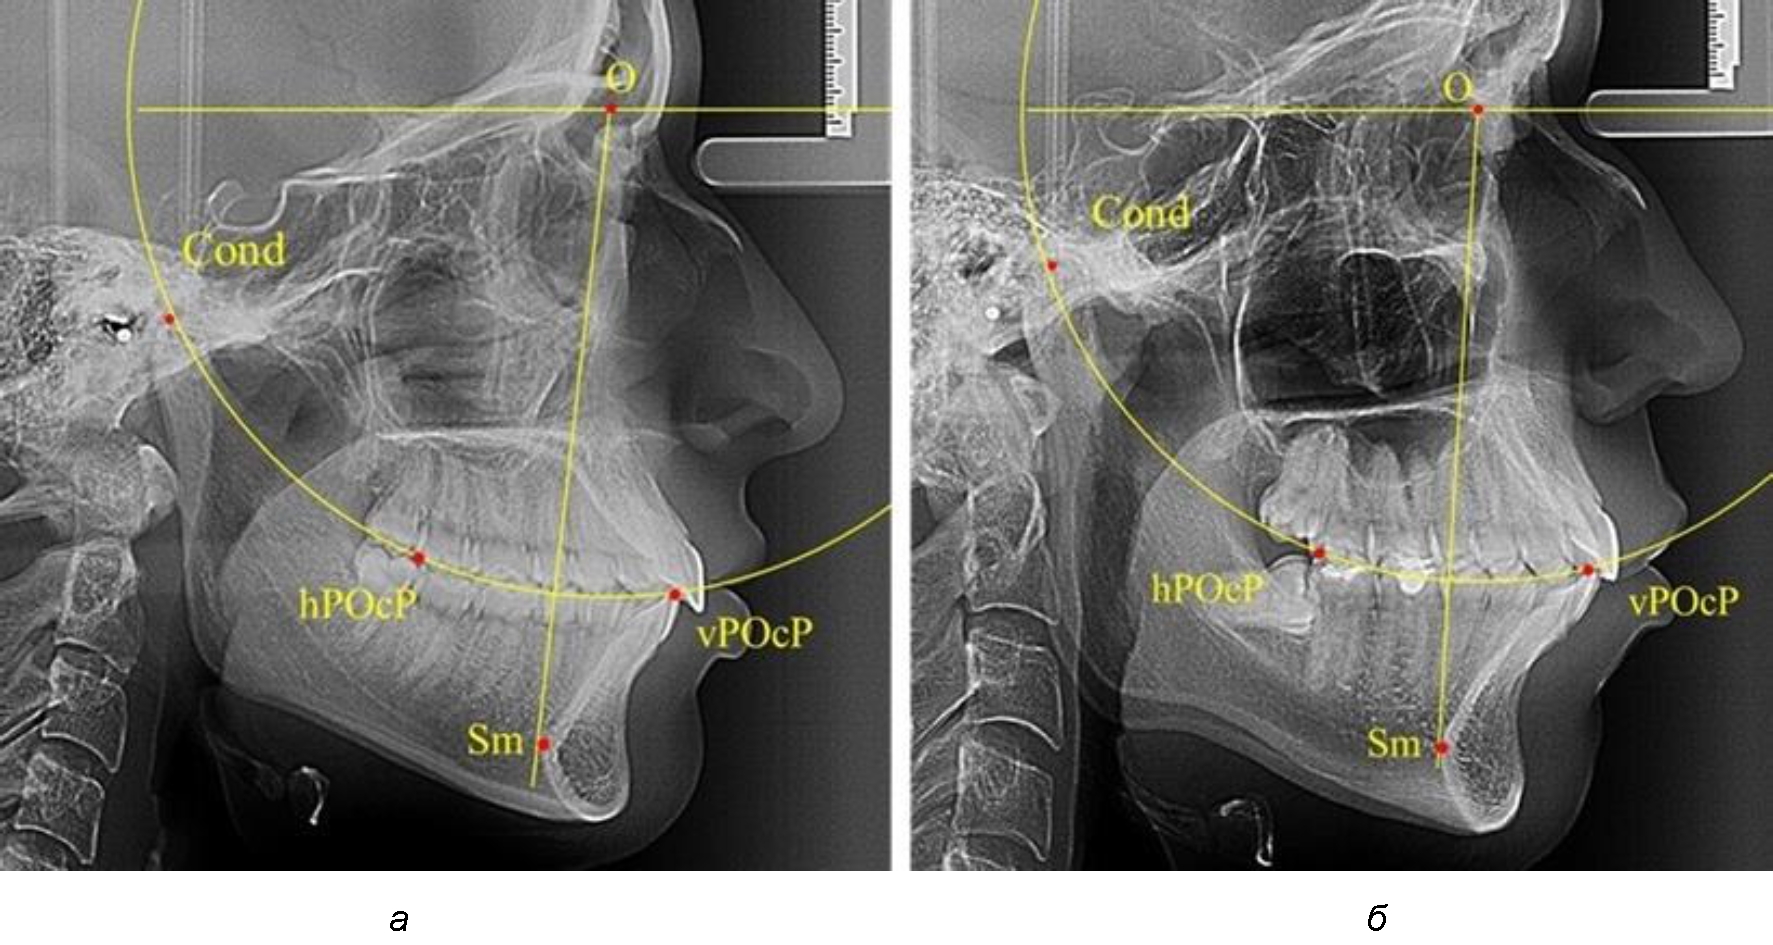

Анализ снимков проводили с использованием традиционного построения стресс-оси по Bimler. Для удобства построения использовали компьютерную программу PowerPoint. Основными точками для построения круга были передняя (vPOcP) и дистальная (hPOcP) окклюзионные точки, а также верхняя выпуклость суставной головки (Cond).

Вставка из программы в виде овала накладывалась на фотографию рентгенограммы и ручным способом растягивалась так, чтобы получился круг, проходящий через обозначенные реперные точки.

Центр окружности О, соединяющей точку резцового перекрытия с жевательной поверхностью зубов и серединой суставных головок, соединяли с выступающей точкой Sm на внутреннем контуре подбородка (рис. 1).

Рис. 1. Метод анализа ТРГ по Bimler

В норме, по резульатам исследования автора, линия Bimler проходила по вертикальной оси первых премоляров, что мы также расценивали как оптимальное их расположение.

Результаты исследования рентгенограмм с мезотрузионным типом резцов показали, что линия Bimler проходила позади первых премоляров у людей с широким типом подбородочного выступа, однако окклюзия была физиологической и не требовала удаления премоляров, что носило рекомендательный характер при проведении подобных исследований при аномалиях прикуса. У людей со средними формами подбородочного выступа линия Bimler проходила впереди первых премоляров (рис. 2).

Рис. 2. Положение первых верхних премоляров при мезотрузии с широкими (а) и средними (б) размерами подбородка